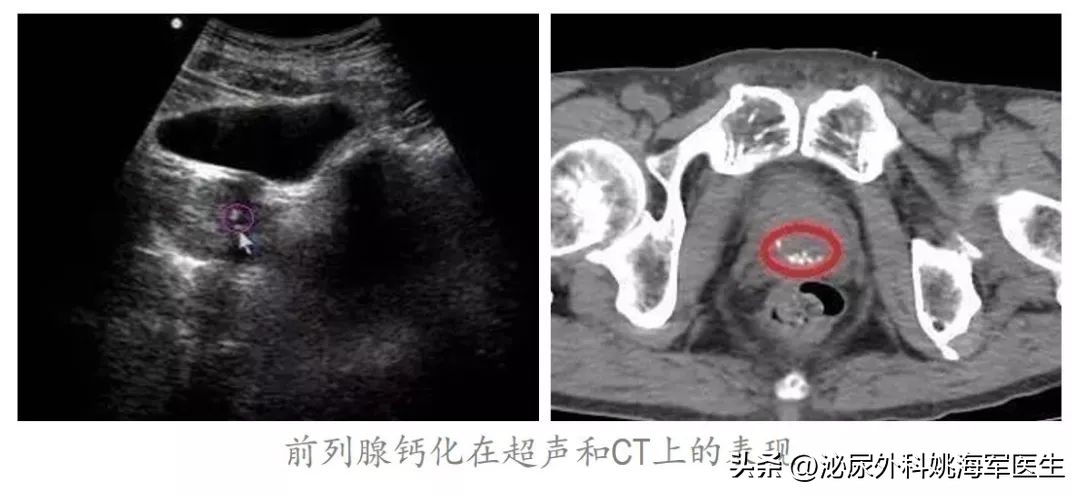

- 前列腺钙化、前列腺结石会导致前列腺炎吗?

前列腺钙化、前列腺结石很多时候其实是慢性前列腺炎长期迁延不愈的结果。前列腺钙化多数是前列腺发生炎症愈合后留下的疤痕,也就是说,前列腺以前有过炎症,现在已经好了,这就如同肺结核自愈后形成的钙化点一样。但前列腺钙化可能会发展成前列腺结石,所以这两者其实是一回事儿,都是指前列腺腺体、腺泡内和腺管内的结石,只不过小的叫钙化灶,稍大的则叫结石。但前列腺钙化或结石的存在,会导致前列腺腺管不通畅,使得前列腺炎迁延不愈。另外还有很多人担心前列腺钙化会不会癌变,目前研究表明,此两者之间没有因果关系。